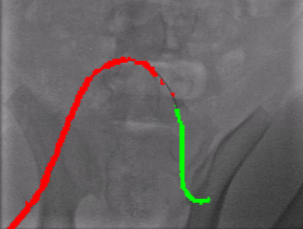

Qualitative Results. Fig. 5 illustrates the catheter and guidewire segmentation results of fine-tuning ViT on our method and different foundation models. The visualization portrays that our method excels in accurately delineating the catheter and guidewire structures, showcasing superior segmentation performance compared to other approaches. This figure further confirms that we can successfully train a federated endovascular foundation model without collecting users’ data and the trained foundation model is useful for the downstream segmentation task.

|

Animal |

Phantom |

Simulation |

Input

Ground Truth

LVM-Med

SAM

CLIP

Ours